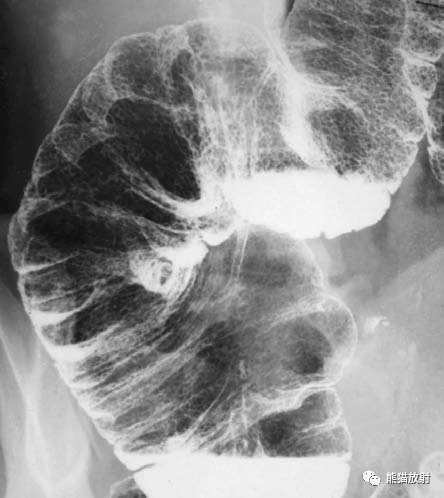

钡餐片子正常图片

钡餐片子正常图片,

去医院检查,被要求吃的"钡餐"到底是一种什么东西?

上消化道钡餐造影前常规胃部点片1

正常食管造影图片